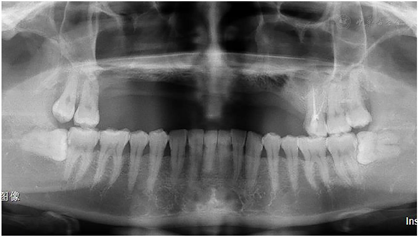

全口曲面断层片示16-25牙缺失(图3)。标准头颅侧位X线片以及头影测量分析结果显示上颌牙槽骨水平向骨缺损伴骨性反颌(图4)。CT结果显示上颌缺牙区牙槽骨缺损,骨性反颌。上颌16牙位窦嵴距离约1 mm,上颌前牙区牙槽骨高度不足7 mm,双侧下颌角肥大,呈方脸形态(图5)。